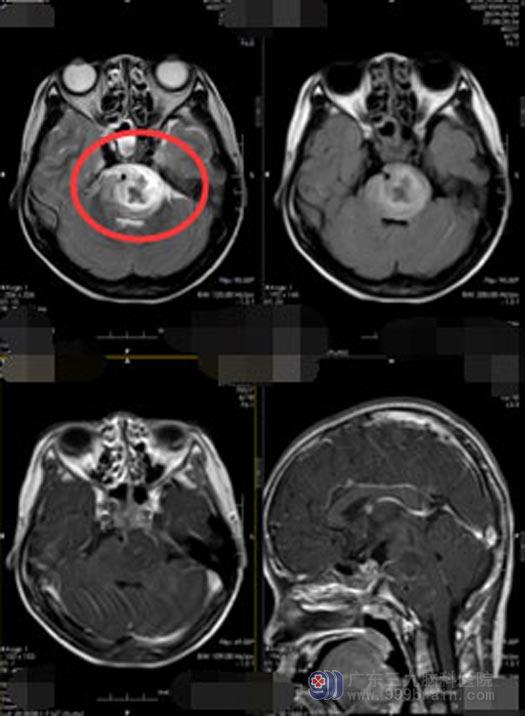

一向活泼乖巧的小梅从几天前开始就没精神,感觉右手和右脚没力气,而且吃啥吐啥。妈妈觉得入秋后天气多变,抵抗力容易下降, 11岁的孩子大概是感冒了。当地诊所医生没发现孩子有感冒症状,建议头部CT扫描,一检查还真发现了问题:脑干占位性病变,脑干明显肿胀,其内周围有块状占位性病变,显示高低混杂信号,包绕基底动脉,最大层面病状范围4.6cm×3.0cm,四脑室受压明显。

进一步的检查后,鲁明副院长初步判断孩子是脑干肿瘤伴脑干出血、吸入性肺炎,需要及时手术治疗。术中显微镜下切开硬脑膜,钩开左侧小脑半球,见左侧的桥小脑角灰白,质软肿瘤组织,切除桥小脑角区肿瘤,对周边的大血管及神经系统保护良好,术程顺利。术后复查CT,无出血,无水肿加重。